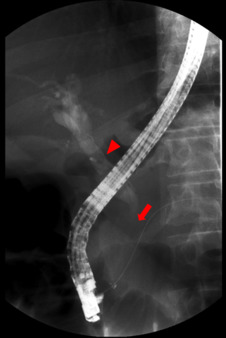

Abdominal CT scan (Fig. 1 ) revealed: a solid lesion on the head of the pancreas, with diameters of 30 mm × 30 mm and lobulated limits, the lesion was most pronounced in the early arterial phases of enhancement, conditioned stenosis of the intrapancreatic portion of the bile duct, and dilatation of Wirsungs channel and main bile duct; Multiple adenopathies larger than 1 cm of diameter; a large solid mass in the left kidney interesting the middle and lower thirds with 9 cm × 7 cm × 6.5 cm diameters, peripheral enhancement and extensive central necrotic area, without evidence of locoregional extension or venous thrombosis.

Contrast-enhanced abdominal CT – images of the lesion in the head of the ...

Fig. 1.

Contrast-enhanced abdominal CT – images of the lesion in the head of the pancreas – hipervascular well delineated lesion on the head of the pancreas – (a) axial and (b) coronal.

The radiologic features of metastatic RCC lesions closely resemble the appearance of primary RCC.11 CT imaging shows lesions that are most pronounced in the early arterial phases of enhancement, which hyperenhancing reflects the hypervascular nature of this tumours.6  and 11 This feature aids in detecting RCC as well as distinguishing it from primary adenocarcinoma of the pancreas, which is typically hypovascular and appears nonenhancing on CT imaging.11 In the case presented, imagological evaluation demonstrated a typical well defined lesion, with characteristic hypervascularity manifested by contrast enhancement. The most common type RCC metastasis, reported in 50–73% of cases, is that of a solitary, localized, encapsulated, well-defined mass. A second pattern of multiple pancreatic lesions has been reported in 5–10% of cases and a third pattern of diffuse metastatic infiltration causing generalized enlargement of the organ in 15–44% of cases.6 Of note, pancreatic neuroendocrine tumours are also hypervascular and contrast avid on cross sectional imaging, such that distinguishing them from RCC metastases to the pancreas can be difficult.21 On MRI, pancreatic lesions typically appear hypointense, compared with normal gland tissue on unenhanced T1 weighted images, both with and without fat saturation.3 Following intravenous contrast injection, homogeneous enhancement is typically demonstrated in smaller lesions and rim enhancement in larger ones.3 On T2 weighted images, the lesions are slightly heterogeneous and moderately hyperintense.19 Hypointense nodules are sometimes visible on T2 weighted images, especially in the diffusely enlarged type.19 Diffusion weighted imaging was recently included in the standard MRI protocol; metastatic lesions typically also show a hyperintensity signal in sequences with high b-values (700–1000).19